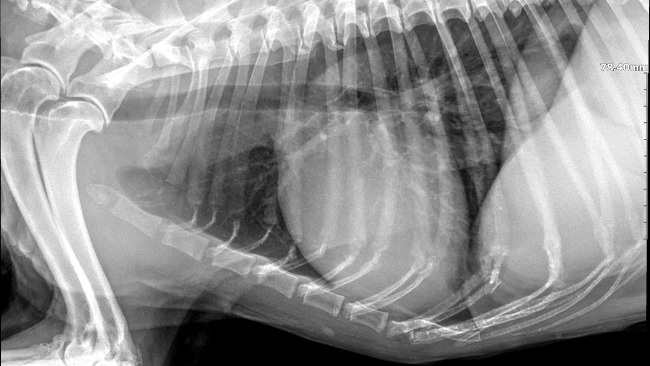

Kiedy do nas trafił, jego stan był dramatyczny. Dziś wiemy już więcej – Kosmo zmaga się z anemią, ma guza na wątrobie, zapalenie pęcherza, zwyrodnienie kręgosłupa. Nie słyszy. Każdy krok sprawia mu ból. Jego wyniki to jedna wielka alarmująca czerwień.

Edit: 8.04 kolejne badania... Echo serca wykazało chorobę serca, poza guzem na wątrobie jest też guz jądra, w drugim płyn. Czekamy na wyniki krwi i moczu żeby postanowić co robimy dalej.